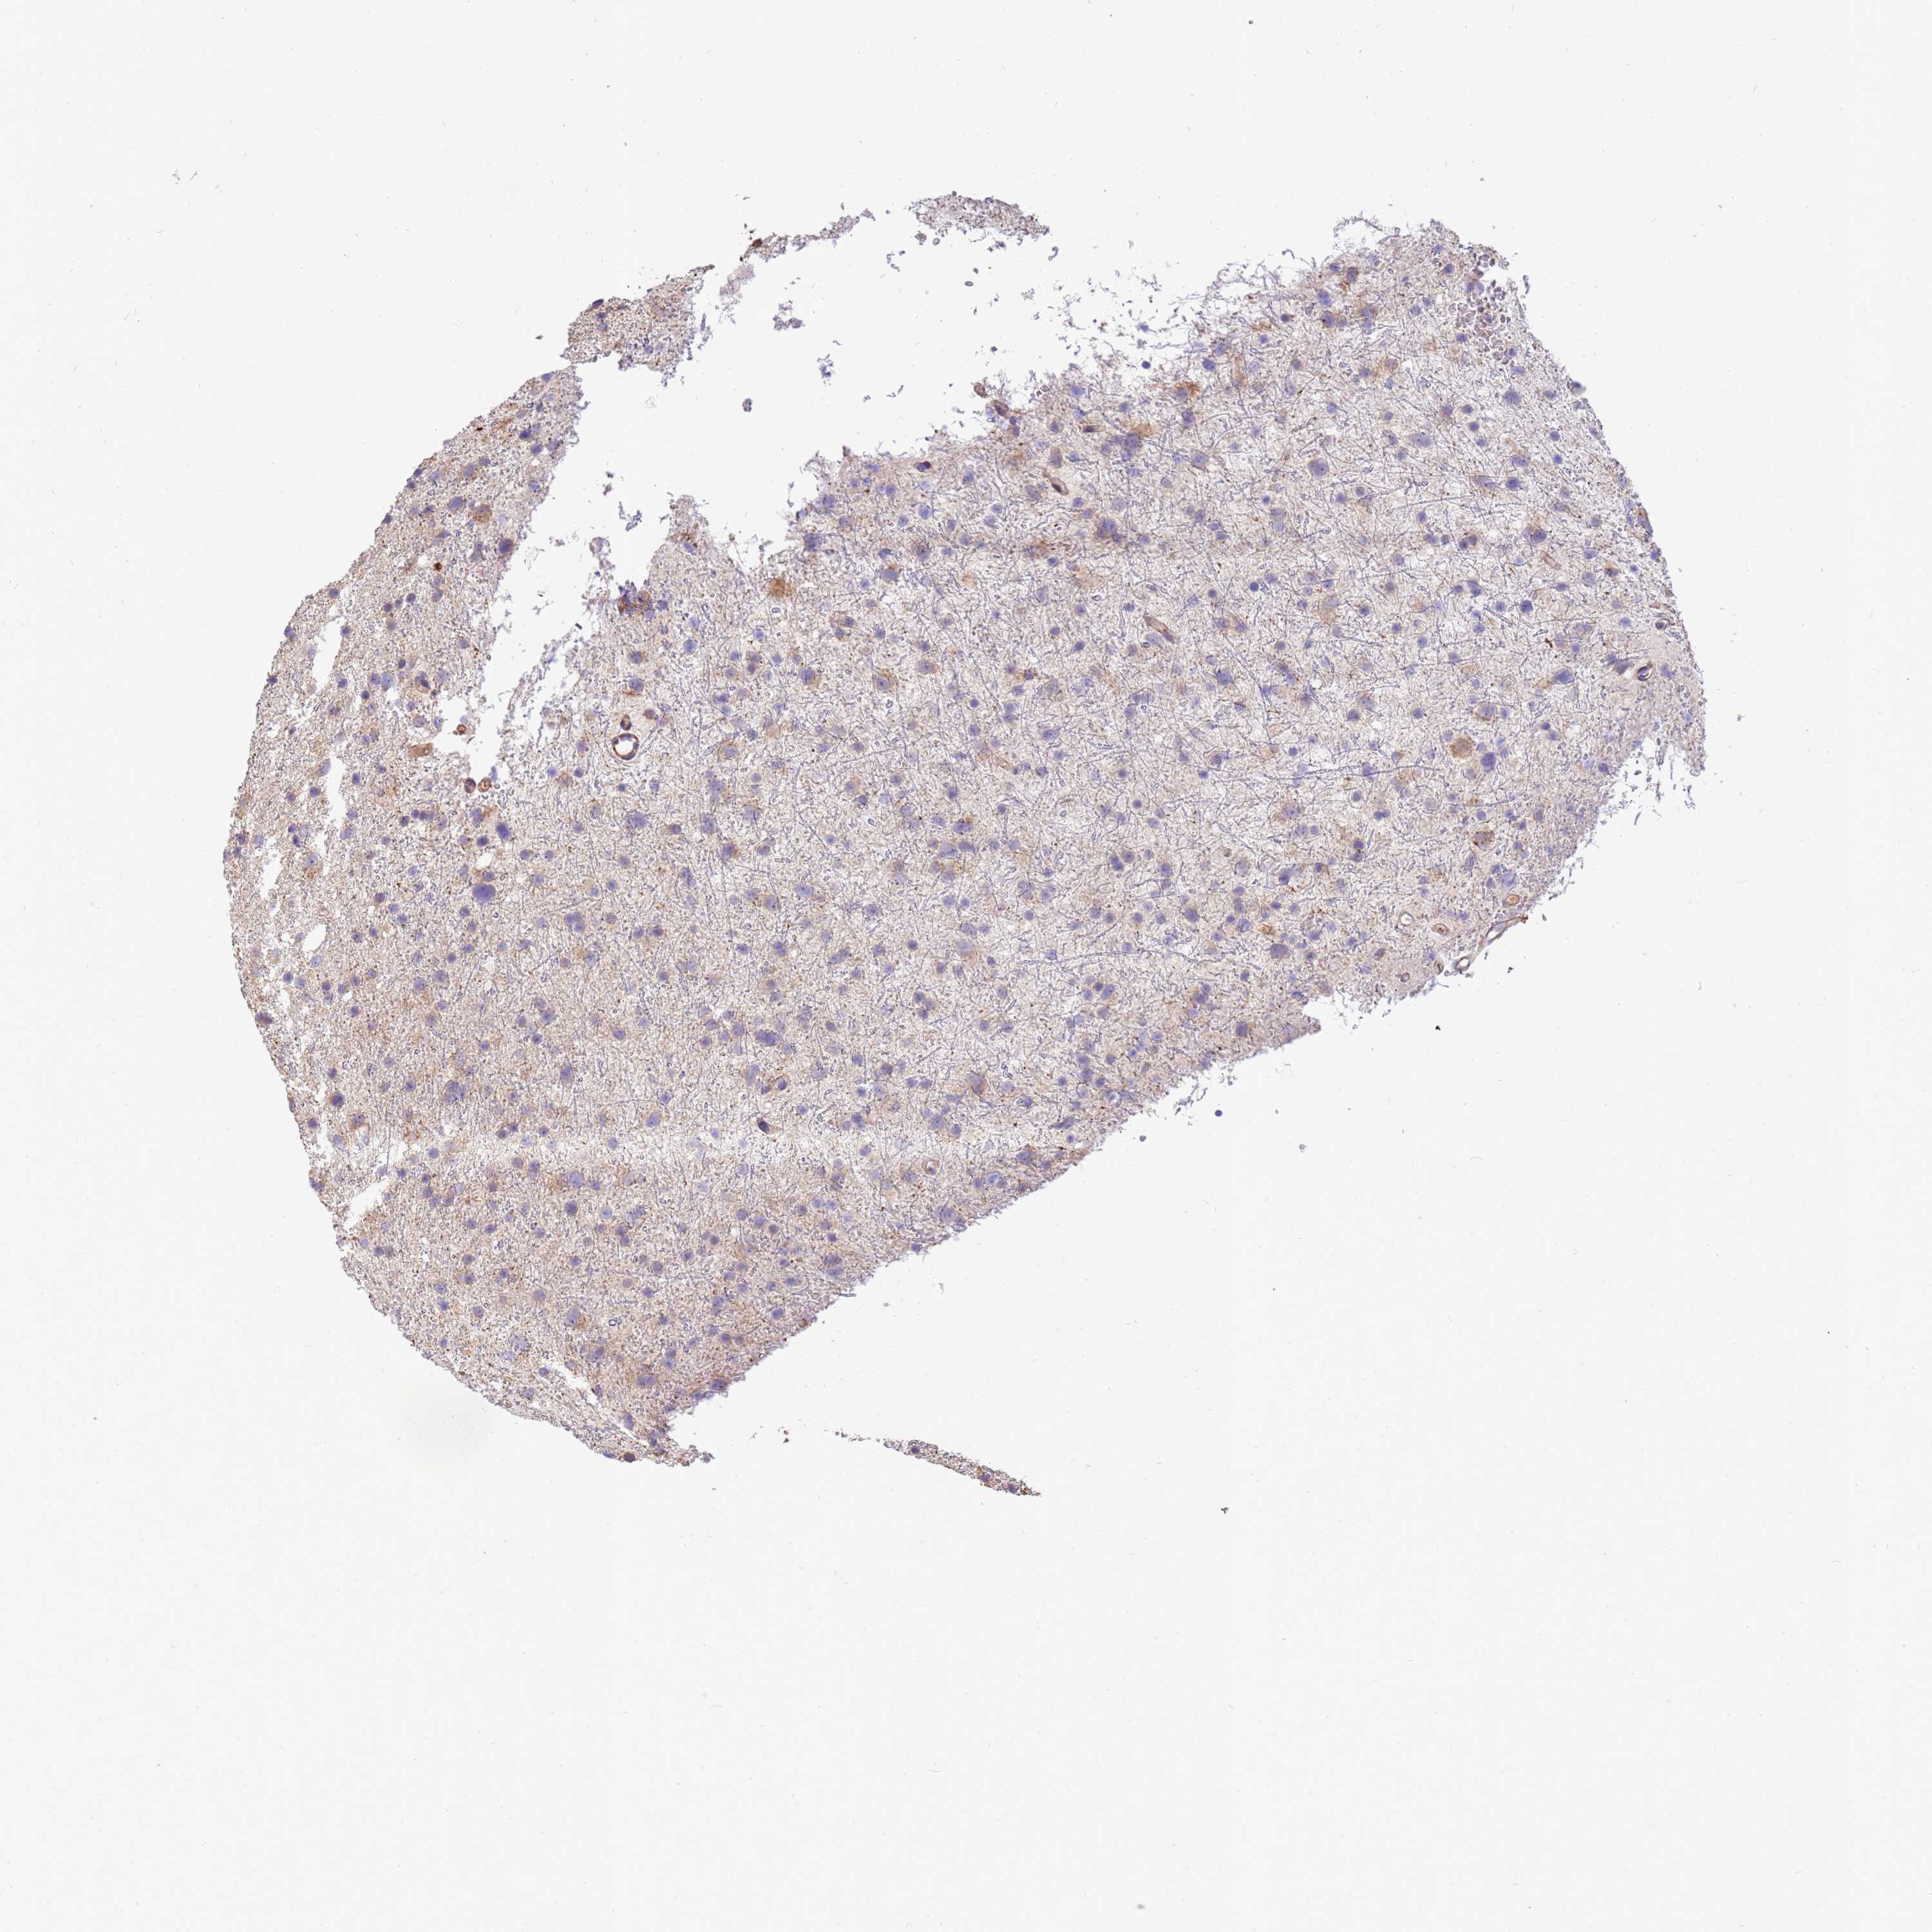

GLIOMA - Protein expressioni

A mouse-over function shows sample information and annotation data. Click on an image to view it in a full screen mode. Samples can be filtered based on level of antibody staining by selecting one or several of the following categories: high, medium, low and not detected. The assay and annotation is described here.

Note that samples used for immunohistochemistry by the Human Protein Atlas do not correspond to samples in the TCGA dataset.

Antibody stainingi

Antibody staining in the annotated cell types in the current human tissue is reported as not detected, low, medium, or high, based on conventional immunohistochemistry profiling in selected tissues. This score is based on the combination of the staining intensity and fraction of stained cells.

Each image is clickable and will lead to virtual microscopy that enables deeper exploration of all samples and also displays staining intensity scores, fraction scores and subcellular localization as well as patient and tissue information for each sample.

Antibody HPA046186

Staining

High

Medium

Low

Not detected

Intensity

Strong

Moderate

Weak

Negative

Quantity

>75%

75%-25%

<25%

None

Location

Nuclear

Cytoplasmic/membranous

Cytoplasmic/membranous,nuclear

Glioma, malignant, Low grade

Glioma, malignant, High grade

Glioblastoma, NOS